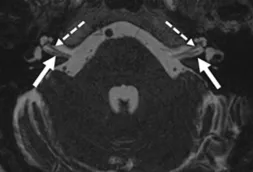

A Steady-state free precession (SSFP) axial image showing the olfactory nerves (arrows).

A Steady-state free precession (SSFP) axial image showing the oculomotor nerves (arrows).

A Steady-state free precession (SSFP) axial image showing the trochlear nerves (arrows).

A Steady-state free precession (SSFP) axial image showing the trigeminal nerves (arrows).